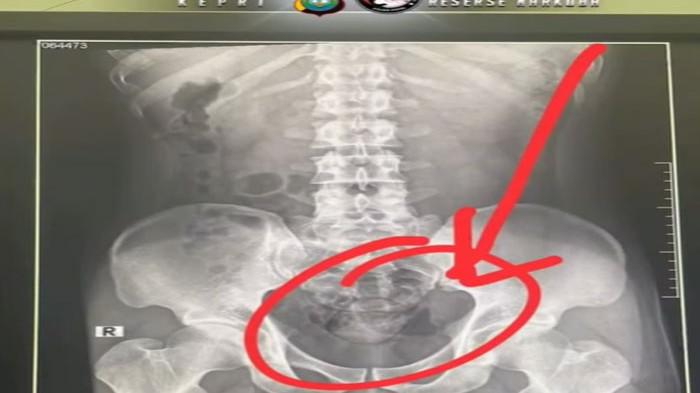

"Yang bersangkutan langsung kami bawa ke Rumah Sakit Bhayangkara untuk rontgen. Hasilnya menunjukkan dua benda asing berbentuk kapsul di dalam tubuh,” ungkap Kapolda Kepri, ,S.I.K.,M.H., melalui Kasubdit II Ditresnarkoba Polda Kepri, AKBP Ruslaeni, Rabu (22/10/2025).

Tersangka kemudian mengeluarkan dua kapsul tersebut di toilet rumah sakit.

Hasil pemeriksaan mengungkap jika narkoba jenis sabu-sabu yang coba ia selundupkan memiliki berat bruto 100 gram.